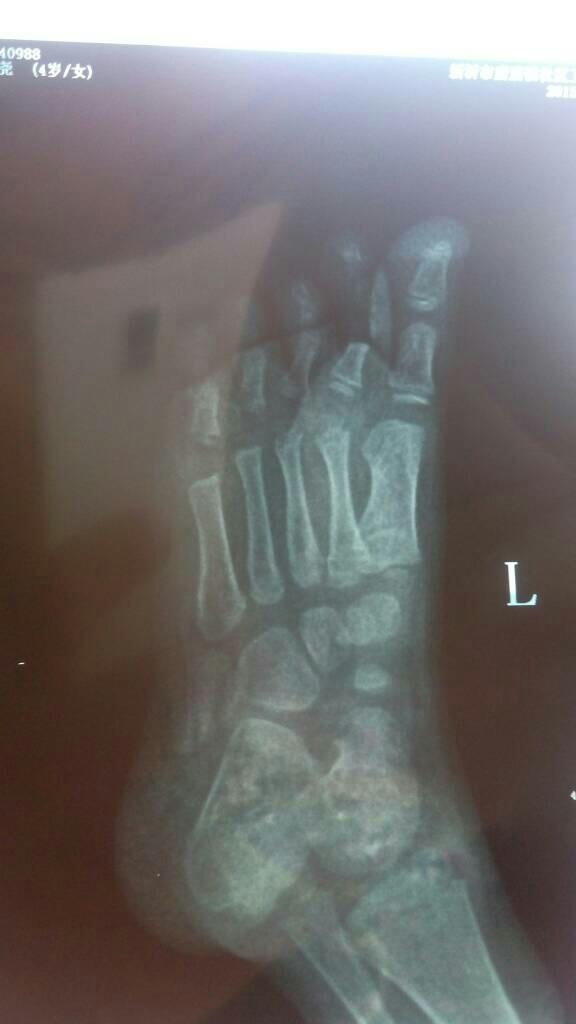

求教外科医生小孩子脚趾头骨折!看一下片子!给点意见 点击展开 匿名用户 2015-10-09 12:28 满意回答 你好,看过图片就是单殖卫纯的骨折没有错位,就外兔敢固定休养一个月就指之丰可以的。 2015-10-09 13:16 宝宝知道提示您:回答为网友贡献,仅供参考。 相关问题 大拇脚趾头骨折吃着药能要孩子会不会有影响 脚趾头拔完骨折穿钉,多久可以走… 脚趾头骨折吃海参好吗?